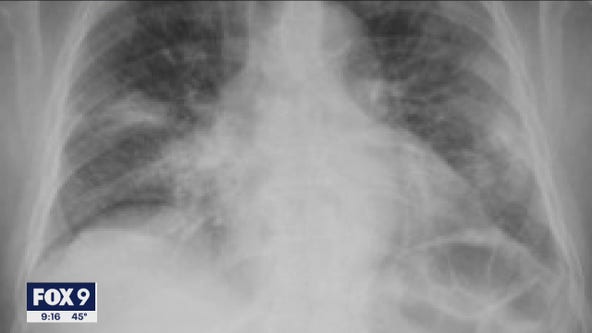

President Trump experiencing "mild symptoms" after he and first lady test positive for COVID-19

President Donald Trump is experiencing “mild symptoms” of COVID-19 after revealing Friday that he and first lady Melania Trump have tested positive for the coronavirus.